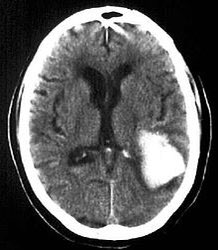

2- Subdural hemorrhage

- Caused by laceration of the bridging corrical veins.

- Crescentic shape in CT scan